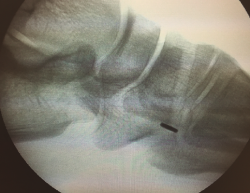

A continuación, se procede a localizar la inserción del TA sobre la cuña medial, diseccionando la región escafocuneana y verificando el punto de inserción mediante escopia.

Figura 4. Preparación de túnel óseo en cuña medial con broca de 4,5 mm y colocación de los hilos en la placa metálica de 4 × 12 mm.

Se realiza túnel con broca de 4,5 mm al nivel de la cortical dorsal de la cuña medial con oblicuidad de proximal a distal hasta llegar a la cortical plantar (Figura 4). Posteriormente, se ensancha el mismo al nivel de la primera cortical según el diámetro del tendón tibial anterior, utilizando una pinza gubia o un avellanador.